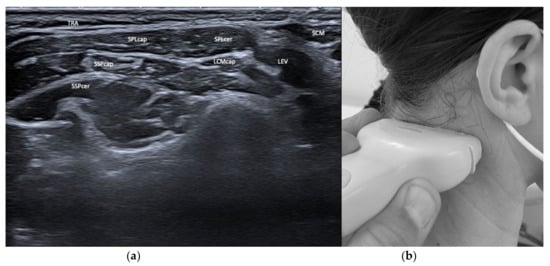

3.1. Layers and Compartments

3.2. Orientation of Layers—Reciprocal Function of Neighboring Structures

| Semispinalis capitis (SSPcap) | Extension of head | + | + | SPLcap, OCI | Strongest extensor muscle of head and neck |

| Semispinalis cervicis (SSPcer) | Extension of neck | + | + | SPLcer, TRA | |

| Splenius capitis (SPLcap) | Ipsiversion of head | ++ | ++ | major occipital nerve, SPLcap/cer, LSMcap, OCI | Prominent reduction in bulk from repeated injections possible |

| Splenius cervicis (SPLcer) | Ipsiversion of neck | +++ | ++ | LEV, TRA, Longissimus cervicis | Relevant for full turn of the neck |

| Longissimus capitis (LCM) | Ipsiversion of head and neck | +++ | ++ | SPLcap, SSPcap | Obligatory USG |

| Levator scapulae (LEV) | Lift of scapula | + | + | SPLcer, TRA | |